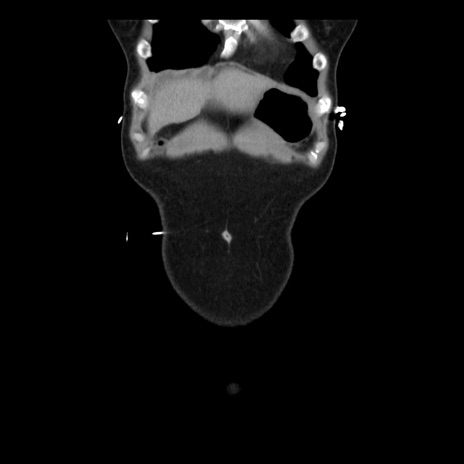

横断像

矢状断像